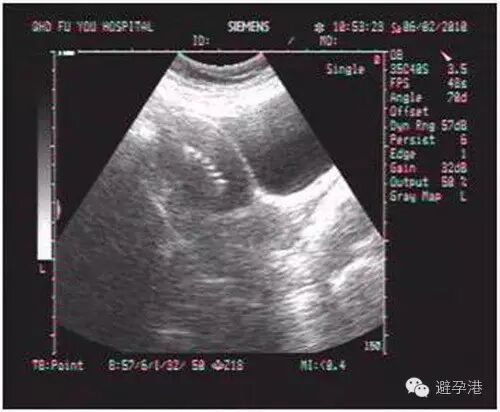

1.纵切面:在宫内可显示出串珠状六个亮点的强回声带。

吉妮致美环怎么样吉妮致美节育器超声图像解读_https://www.jmylbn.com_新闻资讯_第2张